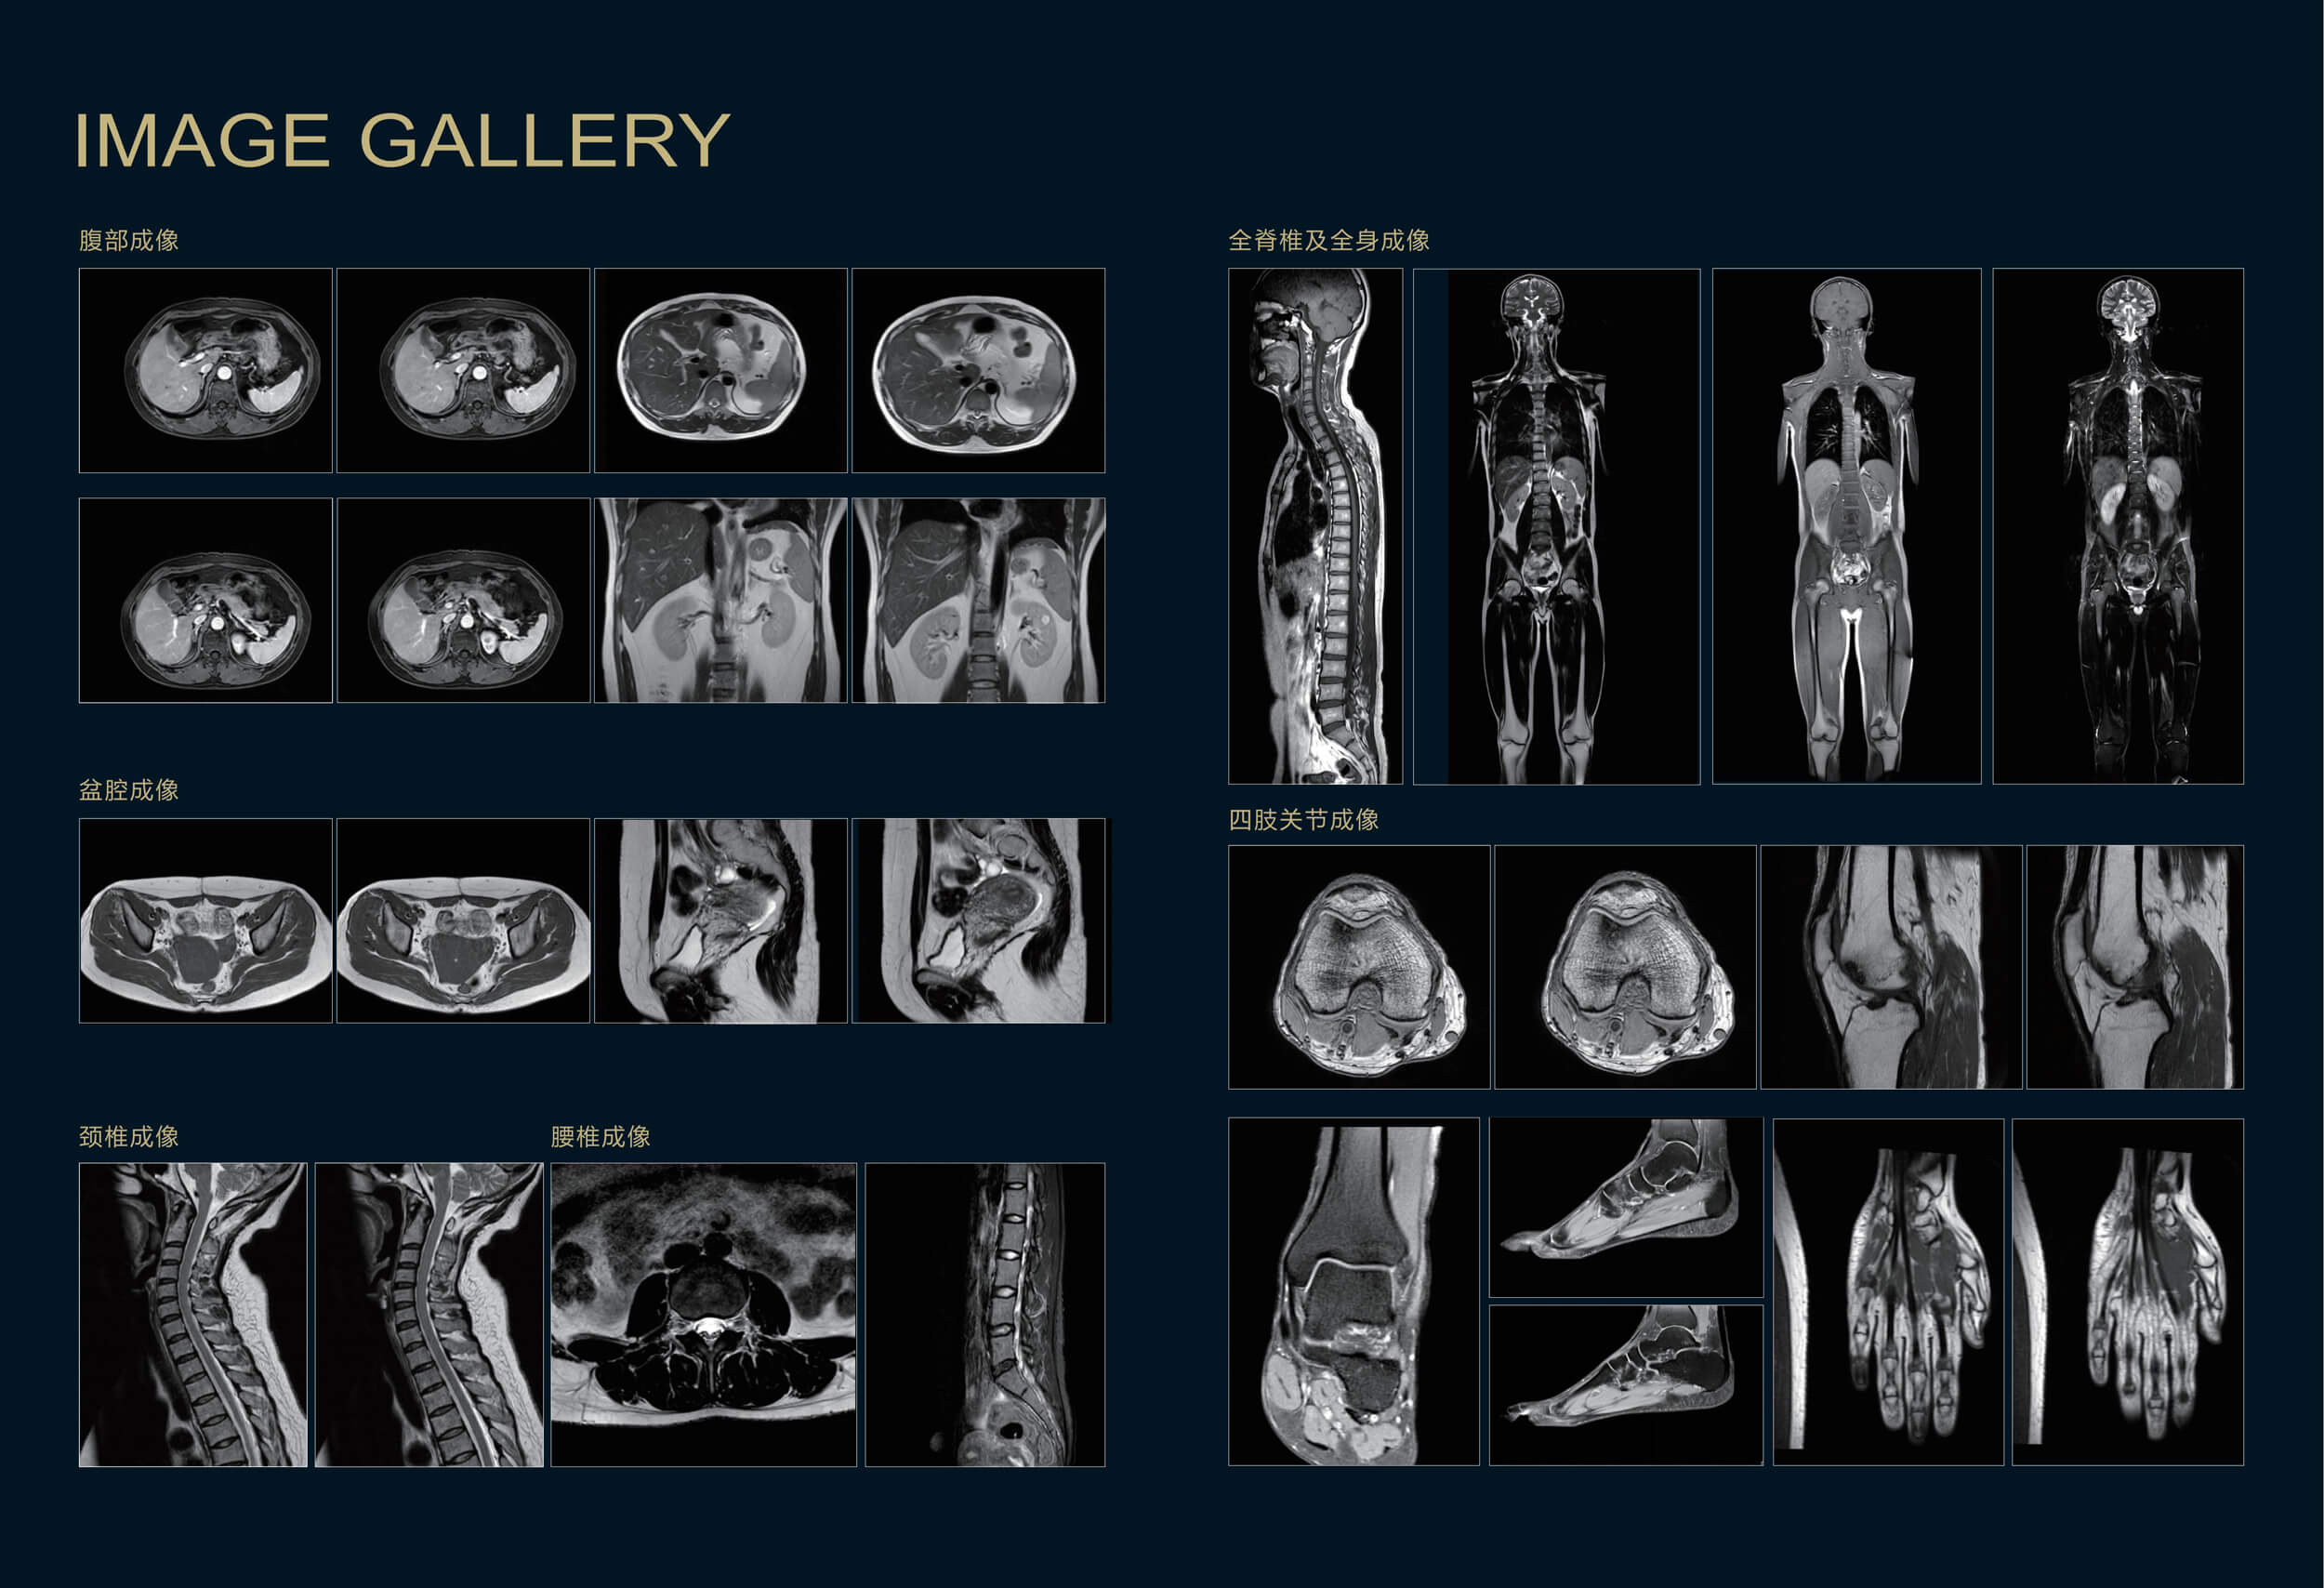

Apsaras飞天1 5t 超导核磁共振系统 先进技术 康达洲际医疗器械有限公司

Apsaras飞天1 5t 超导核磁共振系统 先进技术 康达洲际医疗器械有限公司

康达洲际 Mri